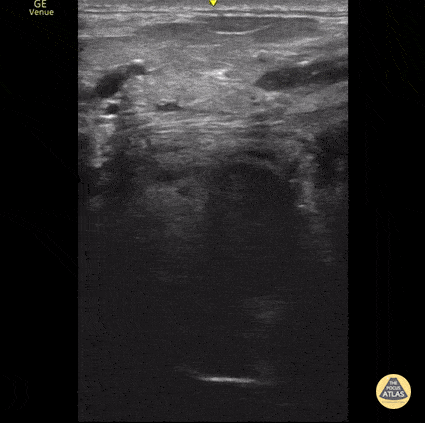

14 year old male presented with pharyngitis, odynophagia, and hot potato voice. He had mild right unilateral tonsil swelling on exam, but was able to tolerate secretions. POCUS images were obtained with a high frequency transducer of the right submandibular area in transverse plane, and demonstrate a tonsil shown as a mixed echotexture structure with hyperechoic invaginations or "crypts", as well as a relatively hypoechoic collection posterior-lateral to the tonsil suggestive of a peri-tonsillar abscess. Contributor: Allie Grither, St. Louis Children's Hospital (Washington University in St. Louis), @AGPemMD